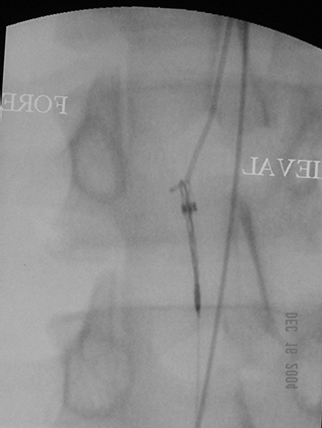

Guidewires can disappear into patients during endovascular interventions such as the insertion of a central venous access. This typically occurs when the operator advances the guidewire and the dilator, sheath, or catheter as a unit, rather than advance these devices over the guidewire. The guidewire is simply a ‘guiding’ tool and should be regarded and employed as such; it is the stem upon which the interventionalist’s tubes and catheters glide to their destination. The wire should be fixed in position as the guided object is slid over it. The images below show the case of a patient from an emergency department in whom a guidewire disappeared into his right common femoral vein during a line placement. It was a 3mm J 0.035 inch guidewire and extended from the groin to the right atrium, but was safely retrieved with a snaring device passed up the inferior vena cava (IVC) from the contralateral groin into the right atrium. In the first image from the left, the guidewire is snared in the right atrium; in the second image, the snare and the wire are pulled into the IVC; the last image is a shot of the retrieved wire (shaped like a shepherd’s hook) and the snaring device (the wire with 3 loops at its end sticking out of a sheath).